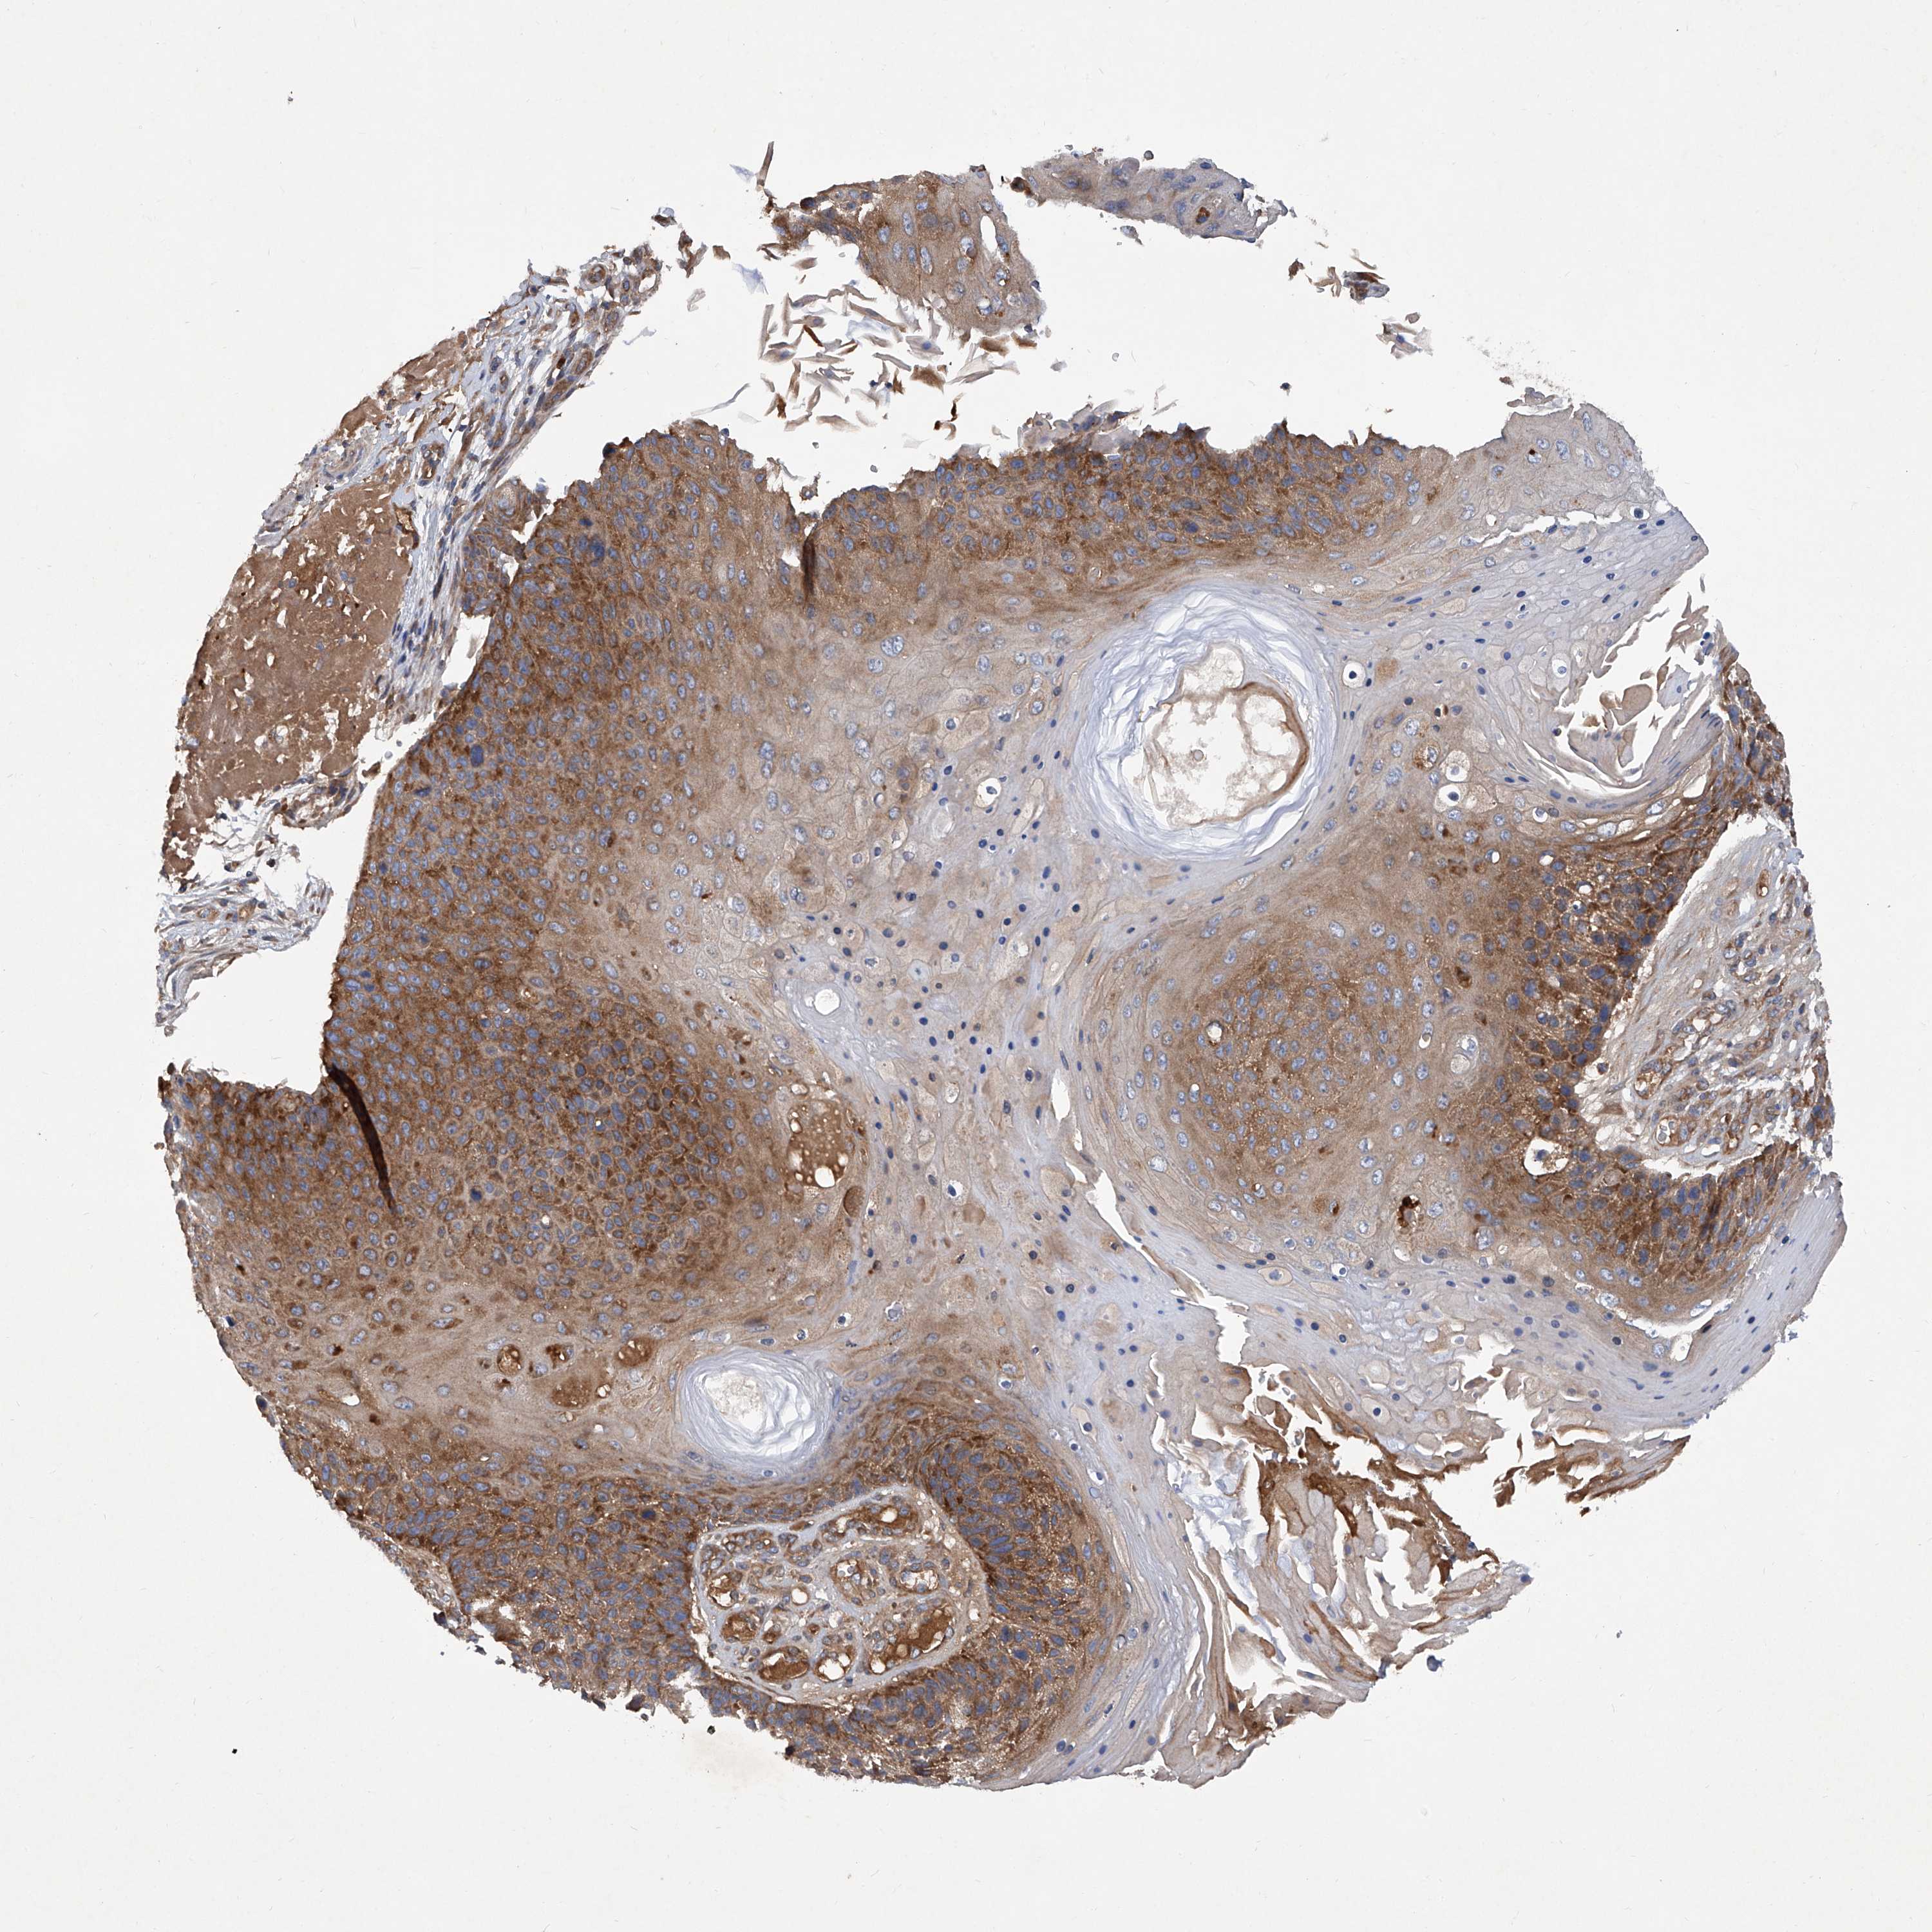

SKIN CANCER - Protein expressioni

A mouse-over function shows sample information and annotation data. Click on an image to view it in a full screen mode. Samples can be filtered based on level of antibody staining by selecting one or several of the following categories: high, medium, low and not detected. The assay and annotation is described here.

Each image is clickable and will lead to virtual microscopy that enables deeper exploration of all samples and also displays staining intensity scores, fraction scores and subcellular localization as well as patient and tissue information for each sample.

Antibody HPA031608

Antibody HPA031609

Antibody HPA031610

Staining

High

Medium

Low

Not detected

Intensity

Strong

Moderate

Weak

Negative

Quantity

>75%

75%-25%

<25%

None

Location

Nuclear

Cytoplasmic/membranous

Cytoplasmic/membranous,nuclear

Squamous cell carcinoma, metastatic, NOS